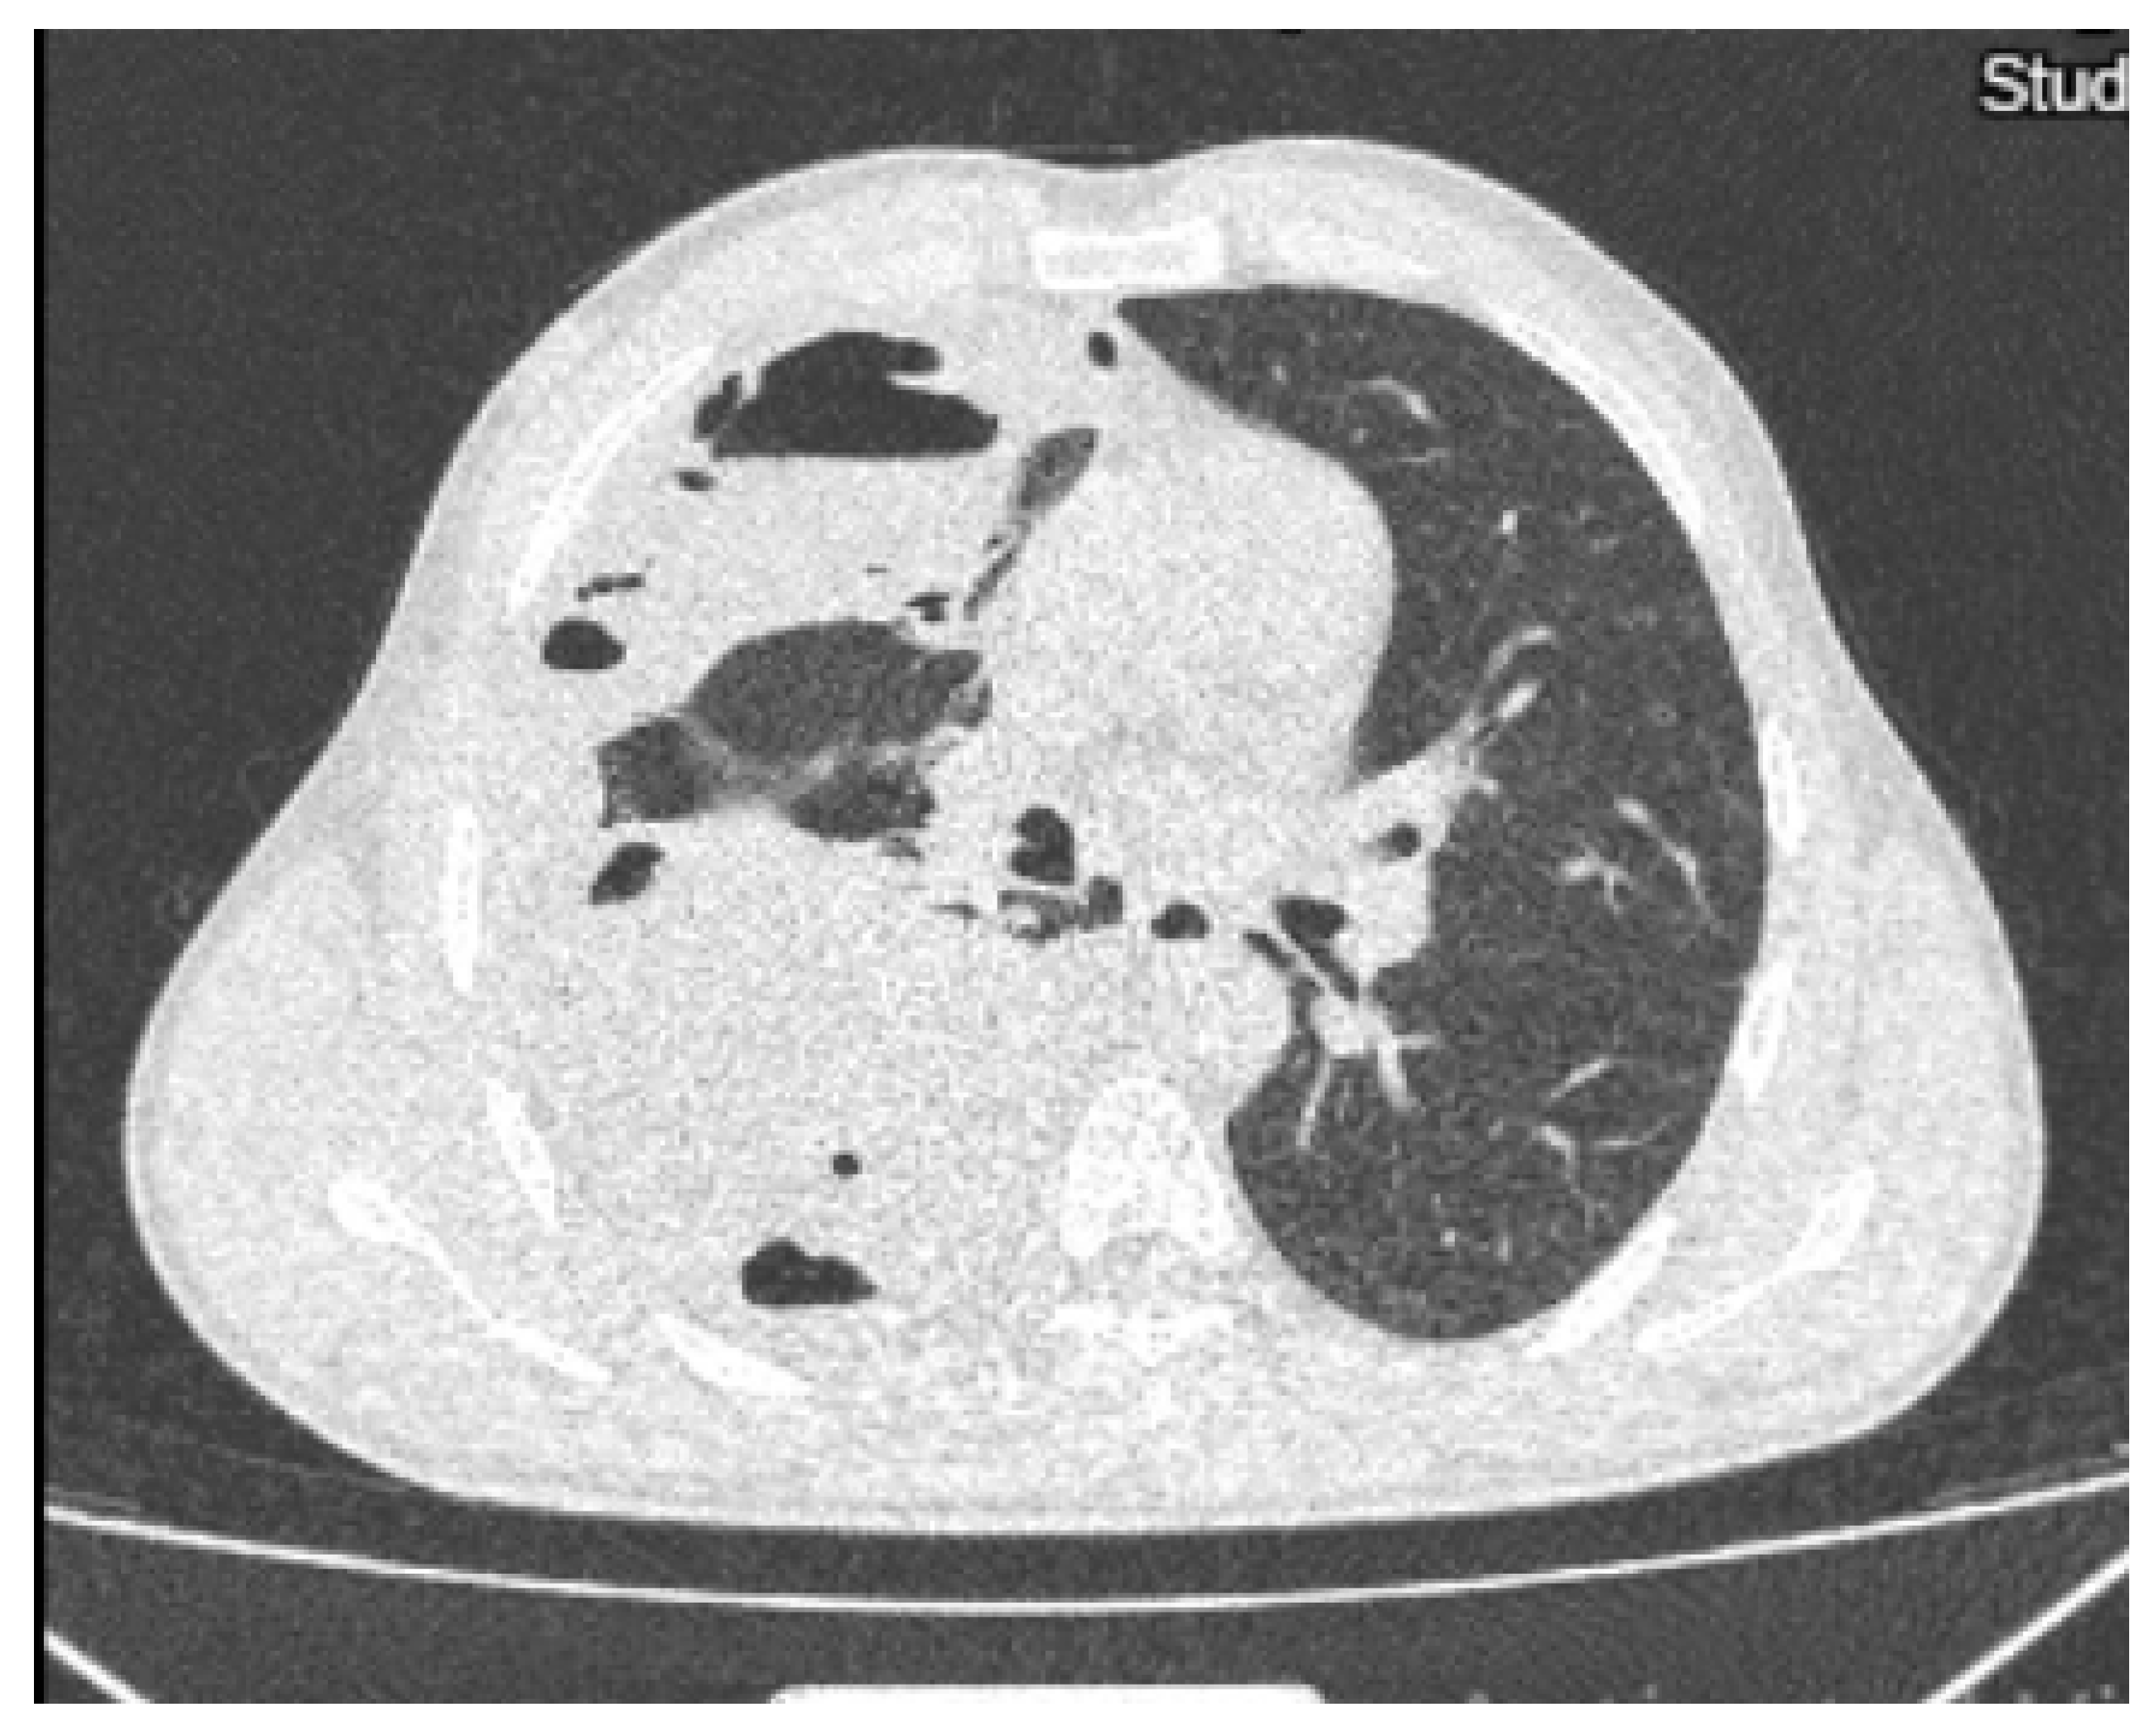

On the twentieth day, the chest X-ray showed multiple hydro-aerial levels up to 85/90 mm on the right lung (Figure 3). A chest computed tomography (CT) revealed free air and fluid levels within the pleural space with collapsed lung parenchyma (hydropneumothorax) and mediastinal lymphadenopaty (Figure 4).

Figure 4. Chest computed tomography showing hydropneumothorax.